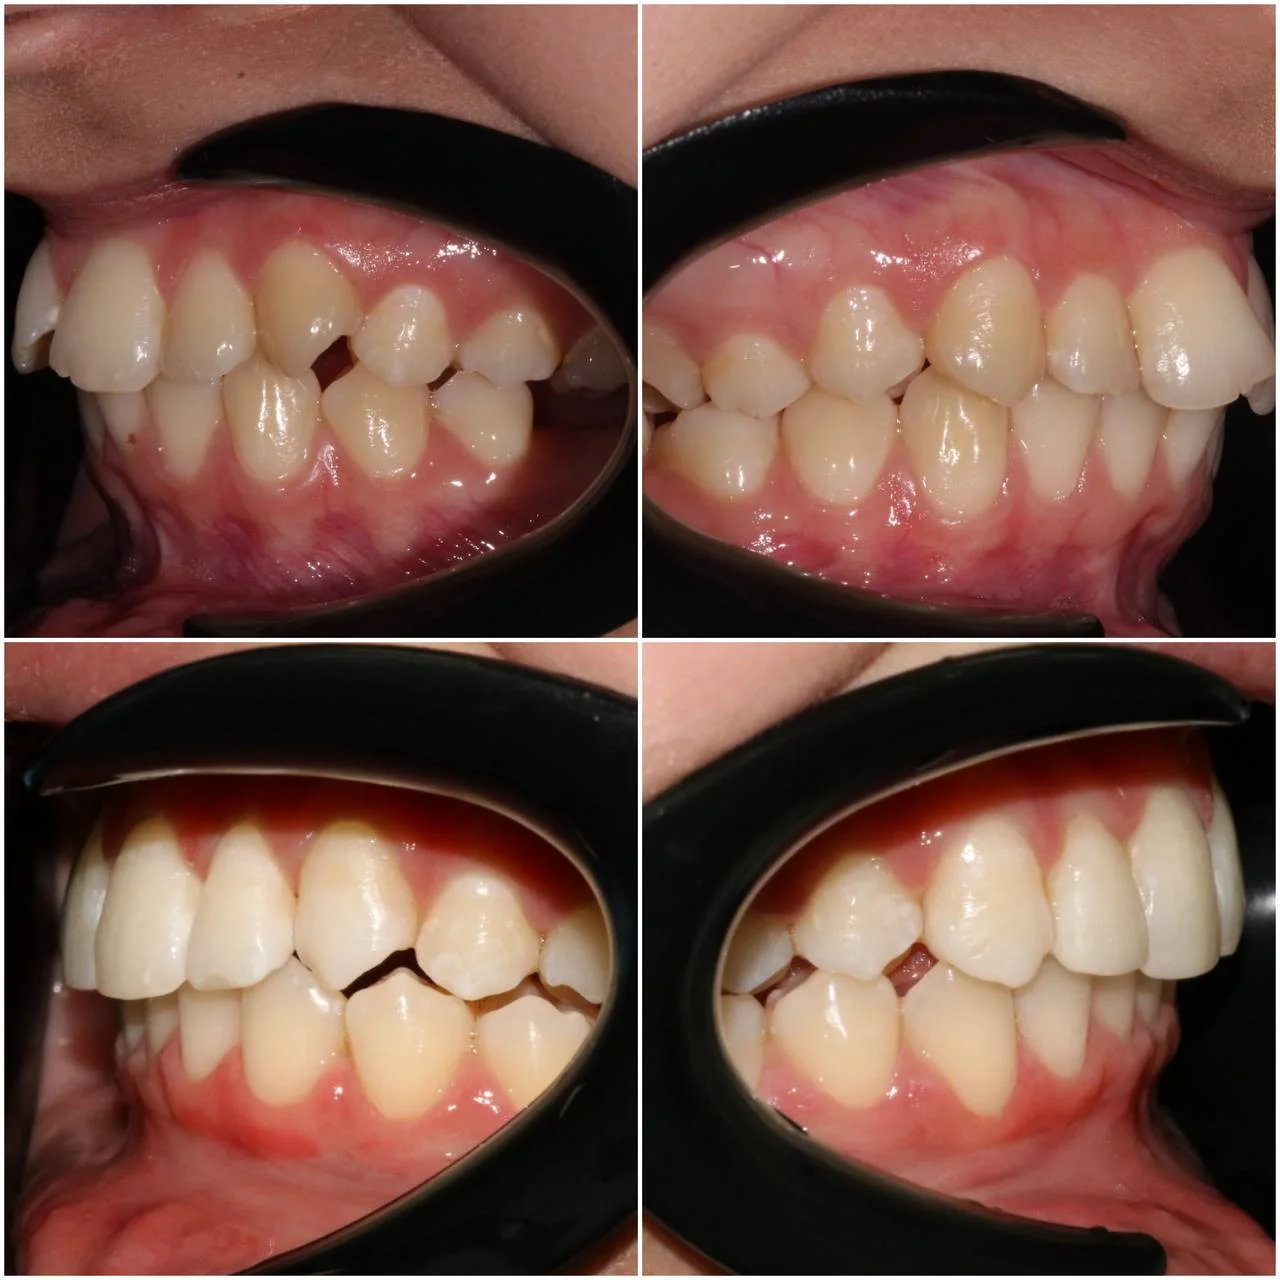

Нарушение соотношения челюстей и неправильное положение зубов — зубные ряды смыкались некорректно, зубы стояли со смещением.

Прозрачные элайнеры 3D Smile на обе челюсти. Выровнять зубы и нормализовать смыкание. Срок — около 2 лет.

Лечение заняло 4 года (март 2022 — март 2026). Капы менялись каждые 1–2 недели, визиты к ортодонту для контроля прогресса и выдачи новых наборов.

Проблема: В клинику обратилась пациентка — беспокоили неровные зубы и неправильное смыкание. Зубные ряды сходились некорректно, зубы стояли со смещением, что влияло и на внешний вид, и на распределение нагрузки при жевании.

Решение: Поставили элайнеры 3D Smile на обе челюсти. Лечение заняло 4 года и потребовало нескольких последовательных этапов коррекции. Капы менялись каждые 1–2 недели, на контрольных визитах отслеживали прогресс и выдавали новые наборы. Зубы встали в правильное положение, смыкание нормализовалось. Зафиксировали ретейнеры на обе челюсти, изготовили ретенционные капы. Пациентка прошла онлайн-консультацию с ортопедом для оценки дальнейших шагов.

Лечение потребовало нескольких последовательных этапов — каждый дозаказ кап уточнял положение зубов, которые не полностью отреагировали на предыдущий курс. Элайнеры 3D Smile позволяют работать поэтапно, корректируя план по ходу. Результат получен, ретейнеры зафиксированы. Рекомендовала пациентке консультацию ортопеда для оценки состояния зубов после лечения